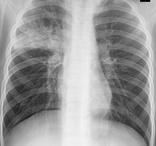

支氣管肺炎是小兒的一種主要常見病,尤多見于嬰幼兒,也是嬰兒時期主要死亡原因。支氣管肺炎又稱小葉肺炎,肺炎多發生于冬春寒冷季節及氣候驟變時,但夏季并不例外,甚至有些華南地區反而在夏天發病較多。支氣管肺炎由細菌或病毒引起。